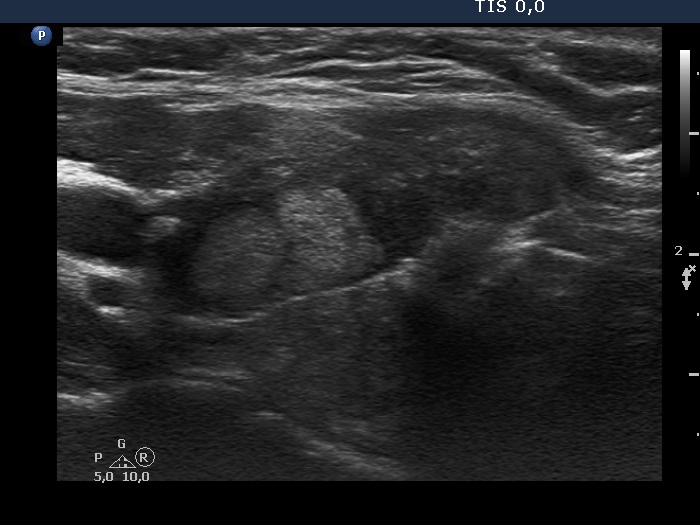

Discrete lesion or nodule in Hashimoto's thyroiditis - case 29 (1125) (ultrasonographic picture 5)

Left lobe, longitudinal view. The echonormal lesions have not regular geometrical shape.